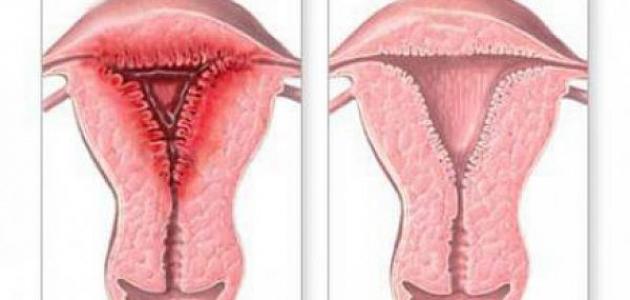

التهابات الرحم أو التهاب بطانة الرحم (بالإنجليزية: Endometritis) هي إحدى المشاكل الصحية التي تصيب بطانة الرحم وتؤدي إلى التهابها، ويكون الالتهاب في هذه الحالة ناجمًا عن العدوى، ويُشار أنّ التهاب بطانة الرحم يختلف عن الانتباذ البطانيّ الرحميّ أو ما يعرف ببطانة الرحم المهاجرة (بالإنجليزية: Endometriosis)؛ فعلى الرغم من كونهما اضطرابين يؤثران في بطانة الرحم إلّا أنّ الانتباذ البطانيّ الرحميّ لا يكون ناجمًا عن الإصابة بالعدوى؛ وإنما عن نمو بطانة الرحم خارج الرحم، والذي ينجم عنه الشعور بألم في منطقتي البطن والحوض،[١] أما الأعراض المرافقة لالتهاب بطانة الرحم؛ فتتضمن ما يأتي:[٢][٣]

وجد أن الإصابة بالتهاب بطانة الرحم لها دورٌ في التأثير في قدرة المرأة على الحمل أو حتى استمرار الحمل في حال حدوثه؛ إذ يشار إلى أن التهابات الرحم قد تؤدي إلى تشكّل الندب، الذي يمنع الجنين من الانغراس أو التطور بشكلٍ طبيعيّ داخل بطانة الرحم، وفي هذا السياق يجدر الذكر أنّ الطبيب المختص بعلاج اضطرابات الخصوبة قد يطلب إجراء فحص للكشف عن إصابة المرأة بالتهاب بطانة الرحم أو يصف لها العلاج المناسب في حال اكتشاف الإصابة، خاصةً في الحالات التي تُعاني منها المرأة من الإجهاض المتكرر، أو الفشل المتكرر لعملية التلقيح الاصطناعي أو ما يعرف بالإخصاب في المختبر (بالإنجليزية: In vitro fertilization) واختصارًا IVF على الرغم من الجودة العالية للأجنّة المستخدمة،[١] فقد بينت دراسة نشرت في مجلّة الطب التناسليّ السريريّ والتجريبيّ (بالإنجليزية: Clinical and experimental reproductive medicine) عام 2016 أنّ الإصابة بالتهاب بطانة الرحم المزمن قد تؤثر في الخصوبة لدى المرأة بطريقتين وهما: منع البويضة الملقّحة من الانغراس في بطانة الرحم كما ذكر سابقًا وارتفاع احتمالية حدوث الإجهاض المتكرّر،[١][٤] وقد أشارت دراسة أخرى تمّ نشرها في المجلة الأمريكيّة لعلم المناعة الإنجابيّة (بالإنجليزية: American journal of reproductive immunology) عام 2018 إلى أنّ ما يزيد عن 50% من النساء اللواتي يعانين من مشاكل في الخصوية يعانين من التهاب بطانة الرحم المزمن، وأنّ خضوعهنّ للعلاج بالمضادّات الحيويّة أدّى إلى انخفاض نسبة الأعراض لديهن بما يزيد عن 80%، وبالتالي ارتفعت لديهن نسبة حدوث الحمل والولادة.[١][٥]